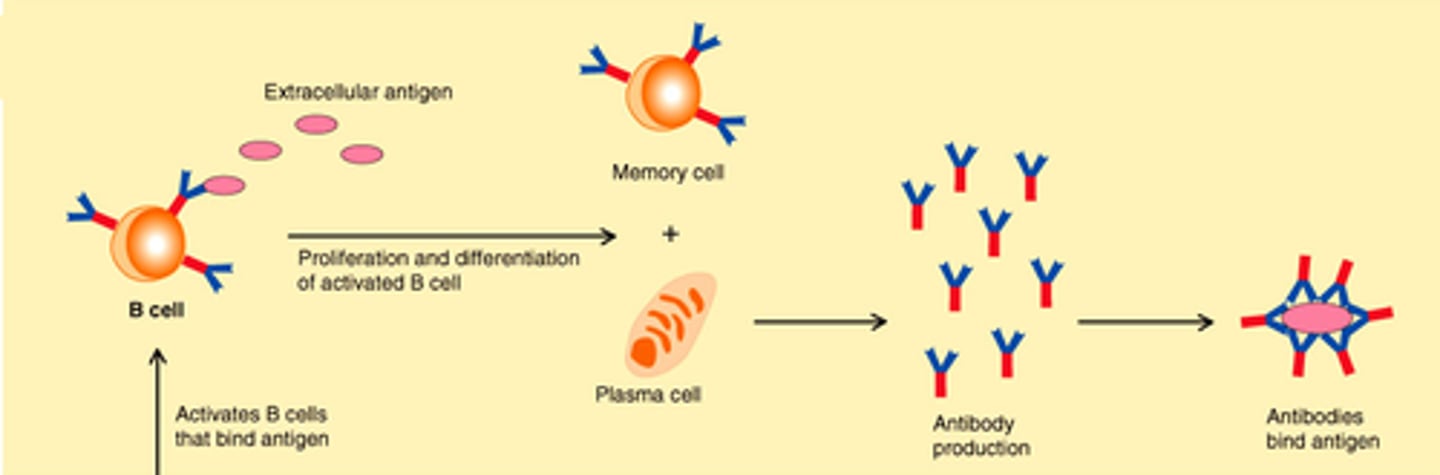

B cells

A type of lymphocyte that is created in the bone marrow; creates antibodies that isolate and destroy pathogens

Naive B cells

A B cell that has not been exposed to an antigen yet

Effector B cells

Active B cells that have been exposed to antigens

Plasma cells

A type of effector B cells, they produce antibodies

Memory B cells

A type of effector B-cell that memorizes the characteristics of the pathogen antigen; it remains dormant until reactivated by the same antigen